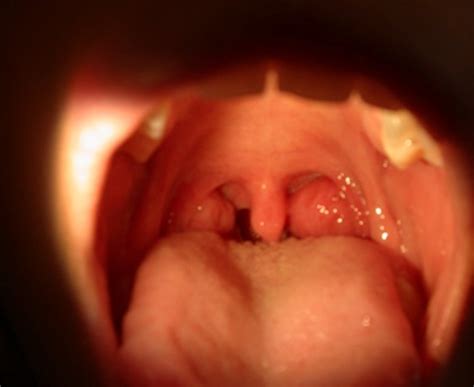

Can Tonsillitis Cause Throat Cancer : Throat cancer / Tonsil cancer caused by abnormal growth.. When symptoms occur, they can resemble those of other illnesses, such as strep throat or tonsillitis. Symptoms of both acute (resolves within a couple of weeks) and chronic tonsillitis (lasts months to years) are are sore throat, fever, headache, fatigue, and bad breath. Chronic tonsillitis:occurs when recurring tonsillitis infections cause chronic sore throat, bad breath and persistent tender cervical nodes. The episodes of sore throat are disabling and prevent normal functioning. Can tonsillitis be a sign of cancer?

Tonsil cancer can cause difficulty swallowing and a sensation that something is caught in your throat. It's most common in children and can be caused by both viral and bacterial infections. Can tonsillitis be a sign of cancer? Tonsillitis is usually caused by a virus, such as a cold, but it can also be due to a bacterial infection such as strep throat. Cancer of the throat can cause the throat to feel sore.

Large Tonsils Bad Breath Hpv Sore Throat | Duoalbarus ... from www.duoalbarus.eu Tonsillitis symptoms often include a sore throat, swollen tonsils and fever. It is caused in the region of the throat and often it is also known as throat diffuse epithelioma. Symptoms may include sore throat, fever, enlargement of the tonsils, trouble swallowing, and large lymph nodes around the neck. The tonsils are two small clumps of lymphatic tissue which hang at the back of the throat. When this is the cause of the spots, the sore occurring on the tonsils and at the back or the throat do not heal. Recognize the symptoms of tonsillitis and how it's treated. Tonsillitis is usually associated with pain whilst swallowing and swollen lymph glands in the neck, whereas coronovirus infections could be associated with cough, fatigue, loss of sense of smell, chest pain mr jayaram specialises in treating neck lumps, throat cancer, tonsillitis and voice disorders. Tonsillar cancer a type of cancer that affects the tonsils, though rare, could be the underlying cause of the white spots.

The tonsils get infected due to viral or bacterial attack. Learn about causes, symptoms, and treatment. Tonsillitis is usually caused by viral infection; The contagious period will depend on the type of infection (viral or bacterial) and treatment. As in rare conditions, tonsillitis may cause swelling in the throat, thereby, breathing difficulty, immediate medical help might be necessary. Being a type of oral cancer, tonsil cancer is rare. Symptoms of both acute (resolves within a couple of weeks) and chronic tonsillitis (lasts months to years) are are sore throat, fever, headache, fatigue, and bad breath. Sore throats are due to acute tonsillitis. Tonsillitis is inflammation of the tonsils in the upper part of the throat. Viruses are the most common cause of tonsillitis. Depending on the extent of the procedure, surgery in the mouth and throat can cause a number of. Can tonsillitis be a sign of cancer? Throat cancer is another type of oropharyngeal cancer.

My niggling sore throat wasn't 'just' tonsillitis, it was a sign of tonsil cancer: Streptococcal infection may cause a. Symptoms may include sore throat, fever, enlargement of the tonsils, trouble swallowing, and large lymph nodes around the neck. It develops as a result of abnormalization of the cells, especially the ones in the oropharynx which is the. Can tonsillitis be an early symptom of cancer development?

Tonsil cancer is a type of oral cancer, and human papillomavirus infection puts patients at a greater risk.

It develops as a result of abnormalization of the cells, especially the ones in the oropharynx which is the. Sore throats are due to acute tonsillitis. The tonsils get infected due to viral or bacterial attack. Including a more sinister process such as cancer. Tonsillitis causes a sore throat but can also cause be accompanied by a head cold and high temperature. In addition to these, there are some risk factors. Tonsillar cancer a type of cancer that affects the tonsils, though rare, could be the underlying cause of the white spots. Tonsillitis is a type of pharyngitis that typically comes on fast (rapid onset). A sore throat caused by tonsillitis. Episodes of sore throat that are disabling and stop you functioning normally. Most cases of tonsillitis go away on their own, but some require medication. The main cause of tonsil cancer in the united states is prior infection with hpv. Can tonsillitis be an early symptom of cancer development?

Tonsillitis is an infection of the tonsils that can cause that tissue in the back of the throat to become red, swollen, irritated, and painful. Sore throats are due to acute tonsillitis. Tonsillitis is caused by an infection of the tonsils. When symptoms occur, they can resemble those of other illnesses, such as strep throat or tonsillitis. Viruses are the most common cause of tonsillitis.

Tonsillar cancer a type of cancer that affects the tonsils, though rare, could be the underlying cause of the white spots.

Depending on the extent of the procedure, surgery in the mouth and throat can cause a number of. Get complete info on tonsillitis (sore throat) from cleveland clinic. Viral tonsillitis is more common and doesn't require antibiotic treatment. Viral causes of tonsillitis do not require treatment with antibiotics and should be cared for by providing supportive treatment including the following Tonsillitis is an infection of the tonsils that can cause that tissue in the back of the throat to become red, swollen, irritated, and painful. Tonsillitis is usually associated with pain whilst swallowing and swollen lymph glands in the neck, whereas coronovirus infections could be associated with cough, fatigue, loss of sense of smell, chest pain mr jayaram specialises in treating neck lumps, throat cancer, tonsillitis and voice disorders. A sore throat caused by tonsillitis. When this is the cause of the spots, the sore occurring on the tonsils and at the back or the throat do not heal. Sue explains how on december 31, 2015 she was told the lump in her throat was a tumour about 1,500 people are diagnosed with tonsil cancer in the uk every year A throat swab or a culture of the tonsils is taken to identify bacterial infection. Squamous cell carcinoma is the most likely form of cancer. Can tonsillitis be an early symptom of cancer development? As in rare conditions, tonsillitis may cause swelling in the throat, thereby, breathing difficulty, immediate medical help might be necessary.